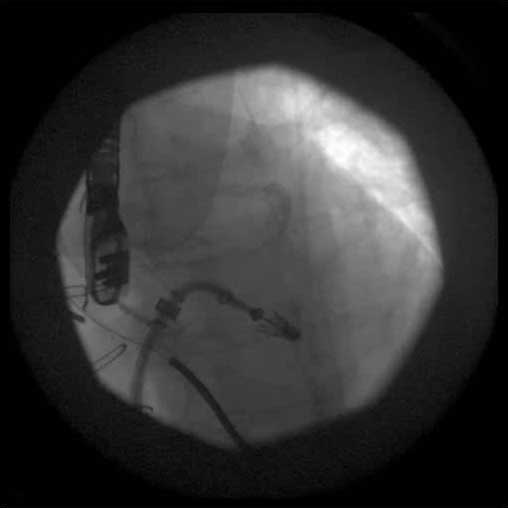

- From the right femoral venous puncture, a TEE guided trans-septal puncture of the septum is performed using a standard transseptal kit (Figure 7) with the Brockenbrough needle, a dilator and a Mullins sheath. The site of the puncture is decided using a standardized approach which optimizes the maneuverability of the delivery system. The puncture is usually high and posterior in the fossa ovalis. After successful septal puncture, the Mullins sheath is parked in the left atrium and the patient is heparinized to achieve an ACT of at least 250 seconds.